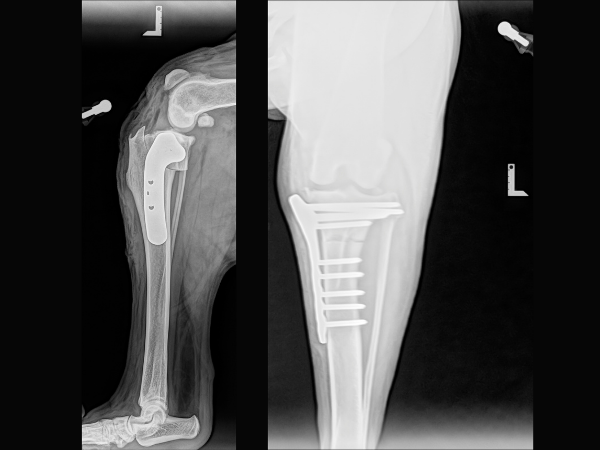

<術前レントゲン>

ファットパッドサインが確認できることから左前十字靭帯の断裂が疑われます。膝関節の中は、通常レントゲンでは黒く写ります。前十字靭帯の変性が進行すると、膝に関節液が溜まり、レントゲンで撮影すると白く写ることをファットパッドサインと呼びます。

<術後レントゲン>

骨切りを実施、脛骨の角度を矯正、プレートで固定することで膝関節を安定させています。